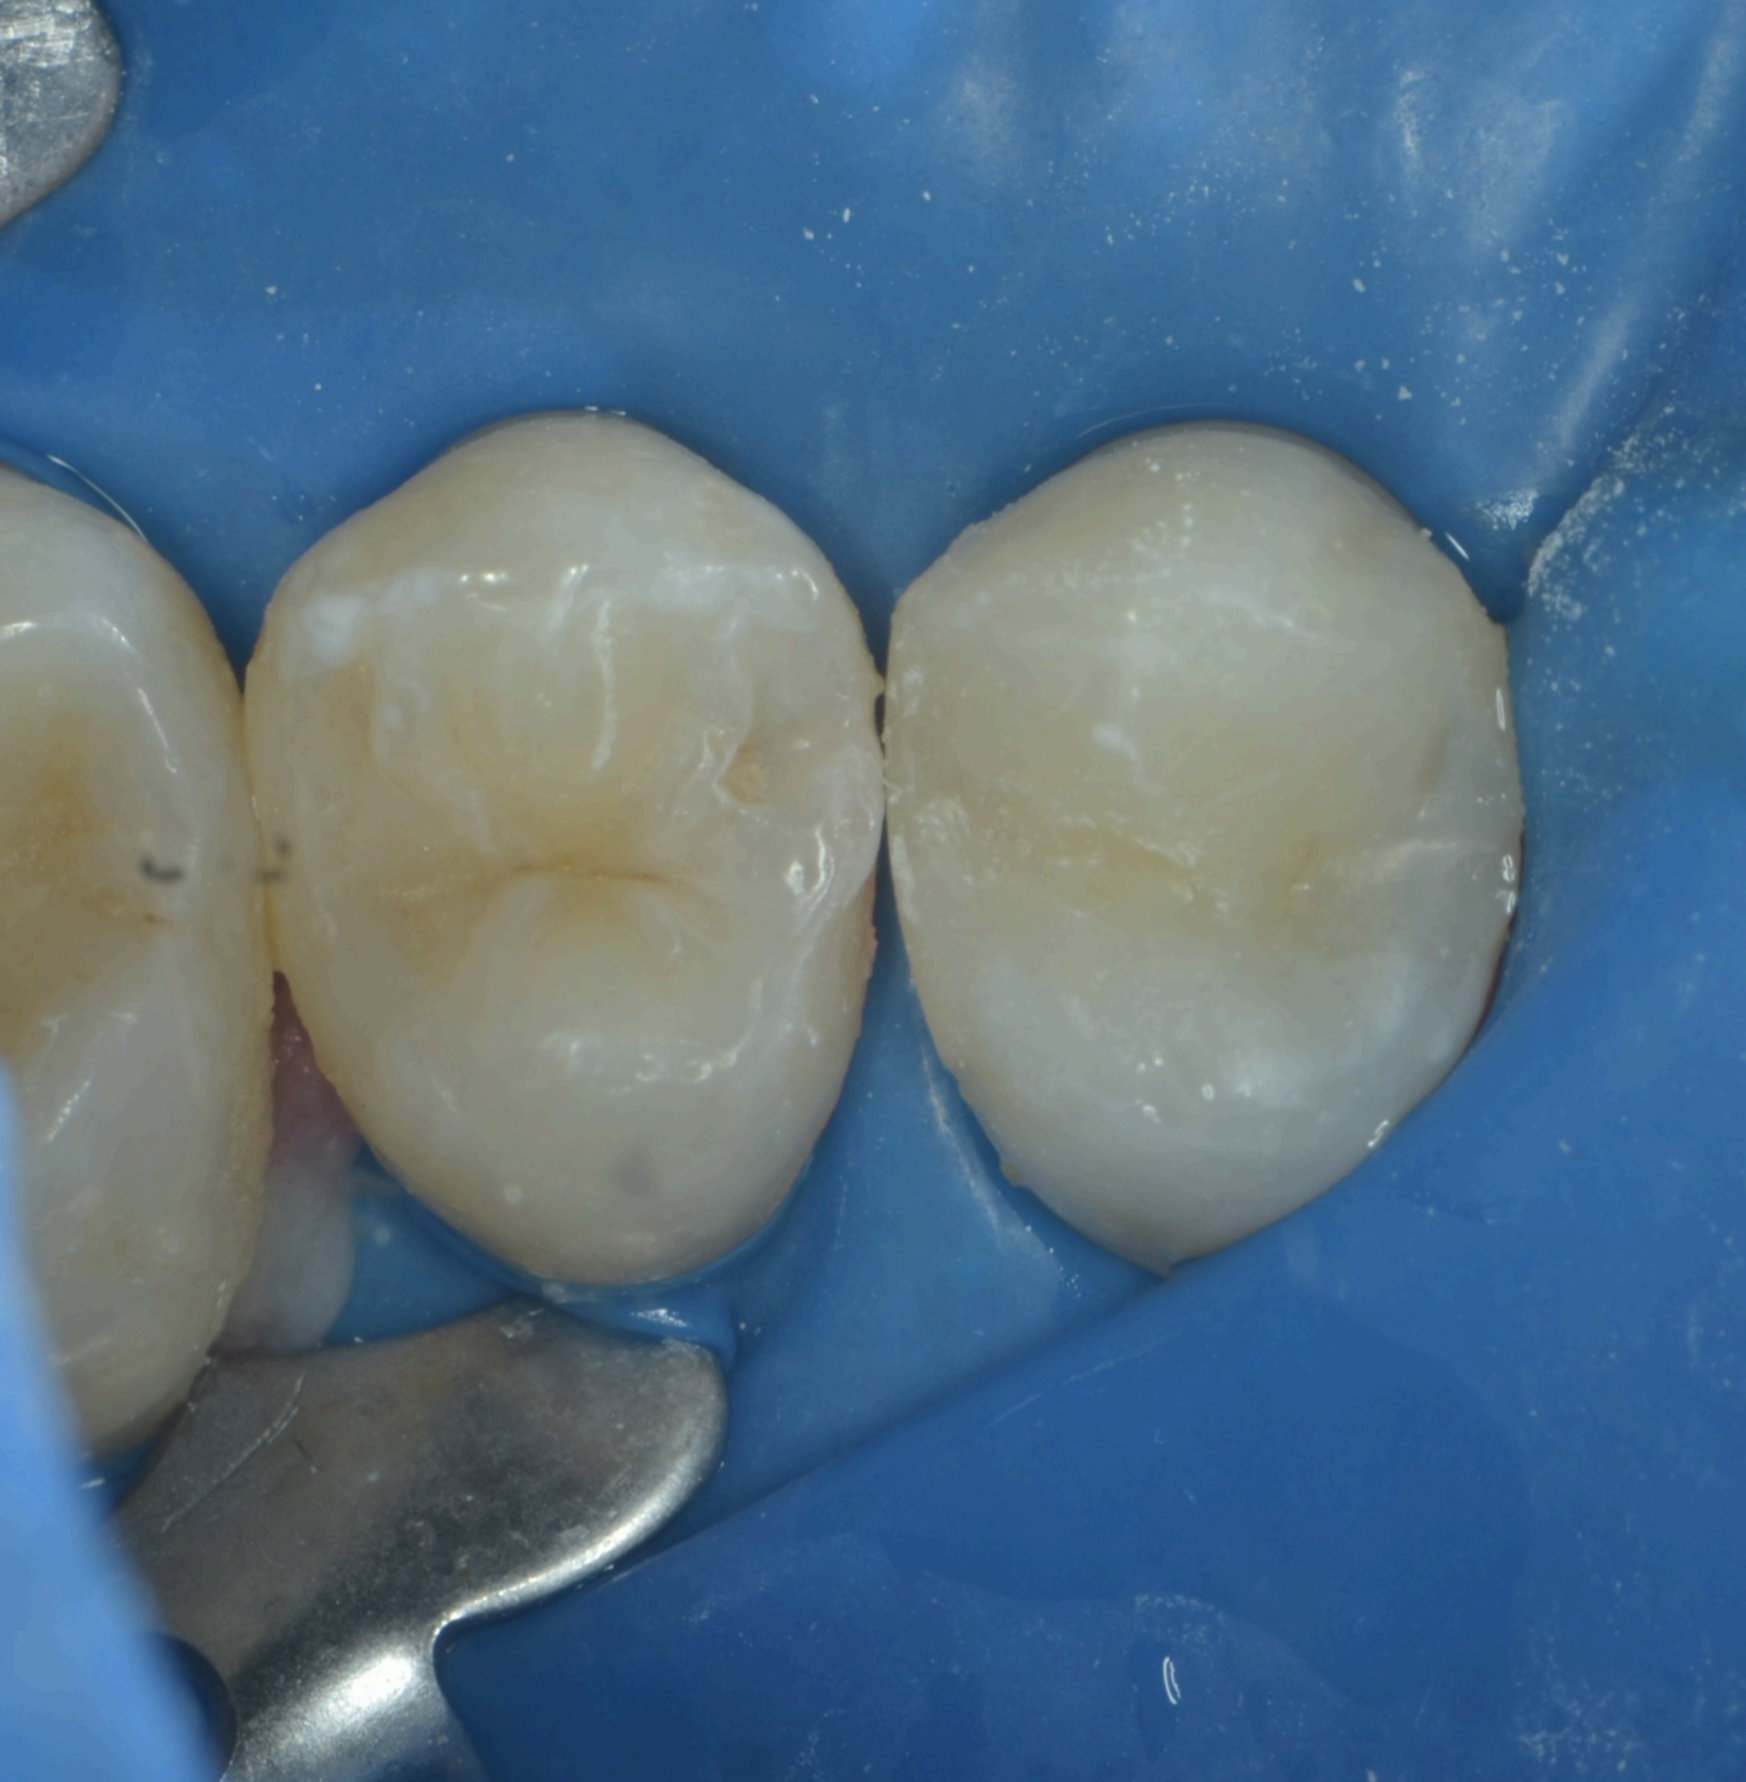

Dupa ce se realizeaza peretele din material compozit estetic, se trece la restaurarea si celorlalte fete ale dintelui din care am indepartat structura alterata, pana ce in final obtinem o forma anatomica si estetica, identica cu cea a dintelui natural. Dupa finisarea noii obturatii, tratamentul este incheiat, urmand etapa de ajustare a muscaturii, in zonele unde materialul este in exces.